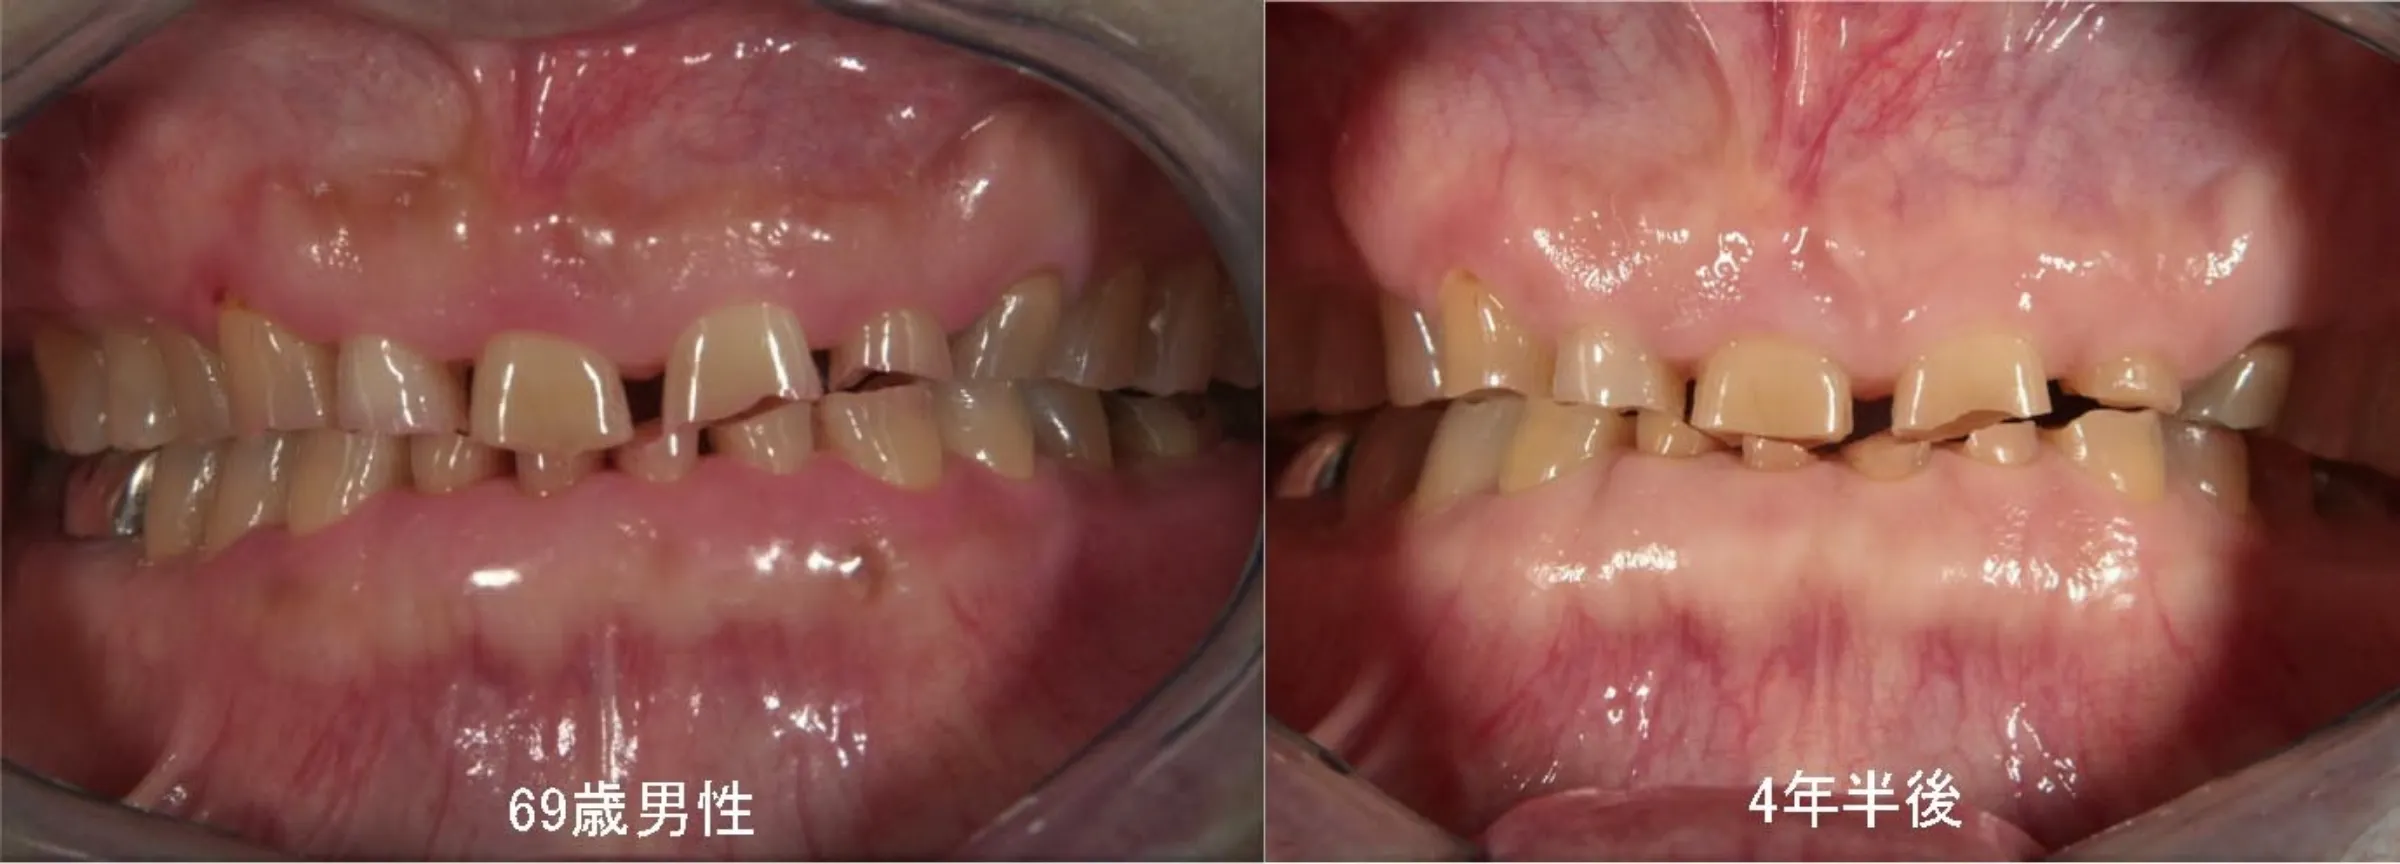

寝ている間の「歯ぎしり」や「くいしばり」を放っておくと、歯がすり減り、歯の神経が出たり、歯が割れたりすることがあります。歯ぎしり等を止める治療は残念ながらありませんが、歯のすり減りや歯の破折の危険性を軽減するために、保険適用で作成できる夜間のマウスピースの使用をお勧めします。

歯ぎしりによって歯が減った症例